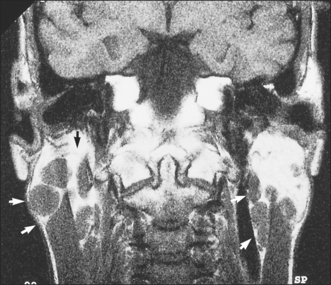

Stone formation (sialolithiasis)

As many as 80% of all salivary stones occur in the submandibular gland or duct (Fig. 14.5), 10% occur in the parotid, 7% in the sublingual gland and the remainder occur in the minor salivary glands. Most stones occur in the submandibular glands because their secretions contain mucus and the viscosity is higher. Of submandibular stones 80% are radio-opaque and can be identified using plain radiographs. Occlusal views are particularly helpful because the image of a small stone must be projected away from other radio-opaque structures such as the teeth and jaws (Fig. 14.6). By contrast the majority of parotid stones are radiolucent and cannot be detected on plain radiography.

Fig. 14.6 Occlusal radiograph, showing the typical appearance of a submandibular stone.

The typical presentation of a submandibular calculus is acute pain and swelling at meal times. Onset is rapid, within a minute of starting the meal, and the swelling resolves over a period of about 1 hour, after the meal is completed. However, this classical picture occurs only when the stone causes almost complete obstruction, often when it is impacted at the opening of the submandibular duct. More often the stone causes only partial obstruction and is lying either within the hilum of the gland or within the duct in the floor of the mouth. In this situation the patient may complain of occasional swelling, often with minimal discomfort, or of a chronically enlarged mass in the submandibular triangle with episodes of dull aching pain. This results from chronic bacterial infection, usually due to S. viridans, arising in an obstructed gland with salivary stasis and poor emptying. Often a salivary stone is totally asymptomatic and is discovered coincidentally during radiography for other reasons.

If a stone is identified on plain radiographs, no other investigation is necessary. If the symptoms suggest a diagnosis of a stone, but the stone cannot be seen on routine radiographs, sialography will be needed. However, this procedure does carry the risk of displacing the stone more proximally in the duct system, to a position where it may be difficult to remove. A radiolucent stone will show as a filling defect in the column of contrast medium and the emptying film will show retained contrast medium proximal to the site of the stone.